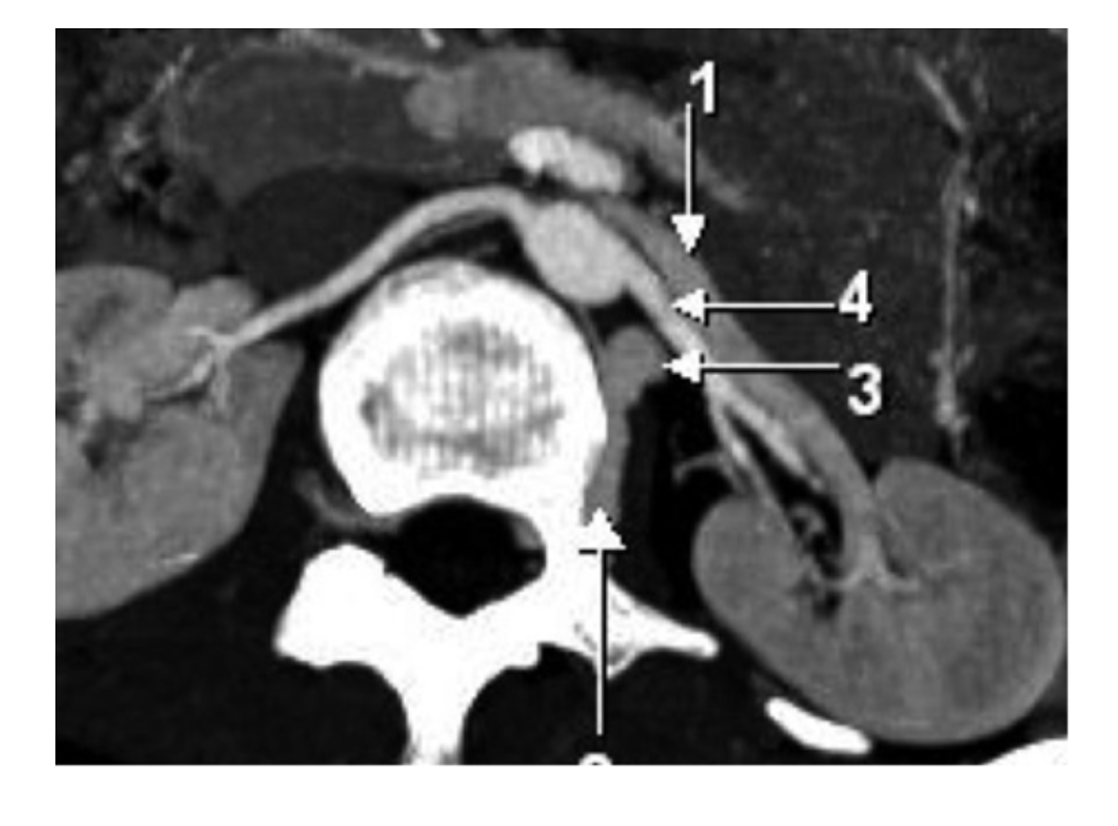

IV

aorta

left renal vein

left renal artery